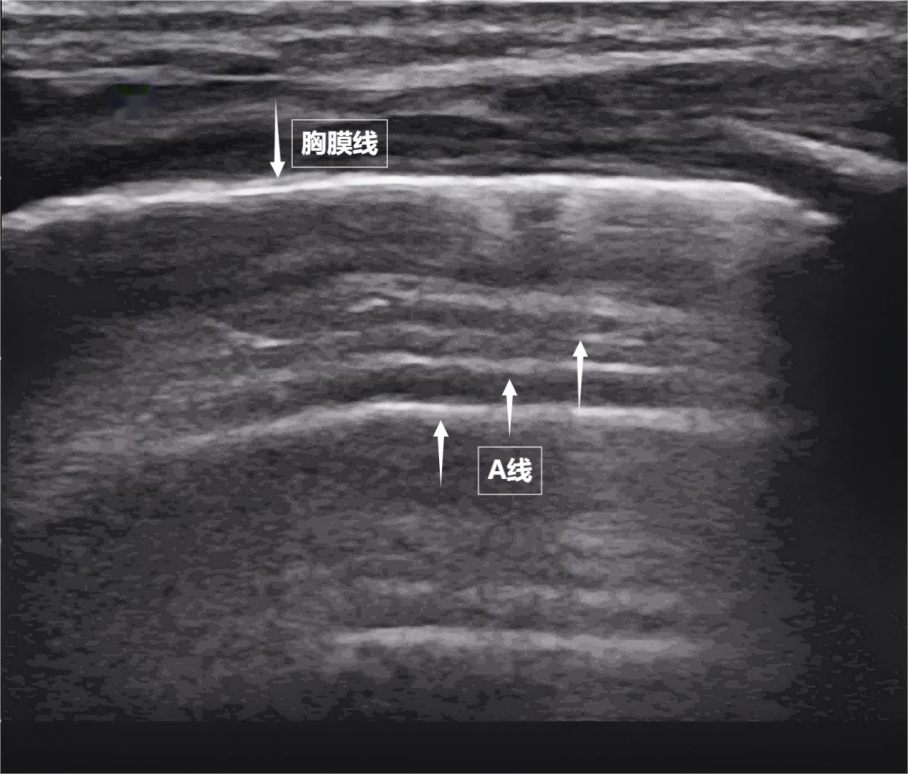

当声波穿过胸壁肋骨缝隙,首先会遇到紧贴肺表面的光滑薄膜——壁层胸膜和脏层胸膜。两者紧密相贴,中间没有多余的气体或液体。它们在屏幕上呈现为一条明亮、光滑的水平线,共同构成了胸膜线。这条线就是肺的“海岸线”。在它的下方,由于肺泡内大量气体对声波的强烈反射,会出现一系列与胸膜线平行的、等间距的、重复出现的明亮平行线,像海浪般不断向屏幕深处延伸,这就是A线(见下图)。A线是正常含气肺部的典型标志。它的存在直接提示肺表面含气充足,胸膜腔内无异常积液或气体。

图为正常新生儿肺部超声表现